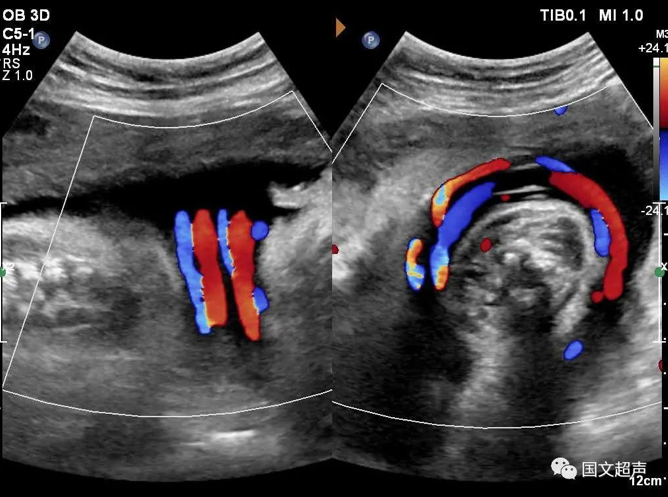

四.關(guān)于臍帶繞頸

臍帶有補(bǔ)償性伸展,纏繞松弛對(duì)胎兒影響不大,但如果纏繞過(guò)緊可影響胎兒血供,有造成胎心率改變、胎兒缺氧、窒息甚至胎死宮內(nèi)的風(fēng)險(xiǎn)。

實(shí)際上影響胎兒預(yù)后的主要因素不在于繞頸的周數(shù),而在于除去繞頸所剩的臍帶長(zhǎng)度。如果孕媽媽只繞頸一周但臍帶相對(duì)過(guò)短,仍可造成不良結(jié)局。

臍帶繞頸的孩子很多,但發(fā)生不良結(jié)局的確占少數(shù),所以不必過(guò)度擔(dān)心,只要每天的胎動(dòng)正常,沒(méi)有突然的增多和減少,定期復(fù)查即可。